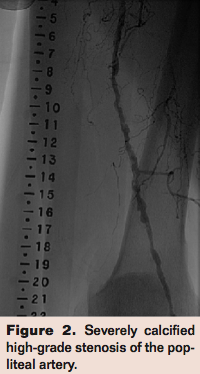

CLI patients tend to have severely calcified arteries, posing a challenge to both surgical and endovascular revascularization techniques. Surgical bypass is feasible in ambulatory patients with a reasonable surgical risk, long occlusions, a patent IP artery that provides direct flow to the foot, and an adequate autologous venous conduit. The candidacy of CLI patients for bypass is often compromised by poor or inadequate length of autologous vein, poor skin nutrition, significant medical comorbidities and calcified, diseased targets. From the endovascular standpoint, one of the most common challenges is the severely calcified lesion that is not dilatable by balloon angioplasty, leading to an unresolved high-grade stenosis (Figures 1-3). These resistant, recalcitrant lesions are also associated with spiral dissections and perforations and can present a physical barrier for the penetration of the antiproliferative drugs delivered by current drug-eluting stents and balloons. They have also been recognized as one of the predisposing factors that lead (in conjunction with forces of contraction, extension, torsion, compression, and flexion) to stent fractures (Figure 4).